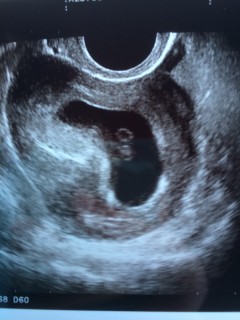

心拍確認ができました♪ 胎芽の大きき5.9mm、その横に卵黄嚢も見えます。 エコーで実際に心拍がピクピク動くのが見れて、安心とともに感動しました。

5w2dでは胎嚢しか確認できなかったので、赤ちゃんが見えるといいなとドキドキしながら病院へ。先生が「心臓が出来てきてるねー」と言って、ペコペコお辞儀しているように動いている赤ちゃんを見せてくれて、心音まで聞かせてくれました。ちょうど一年前心拍確認前に流産しているので、初めて見る心拍に感動して涙が出ました。